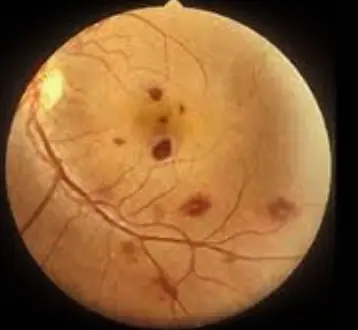

Chorioretinitis,

Differentials

- CMV

- Congenital Toxoplasmosis